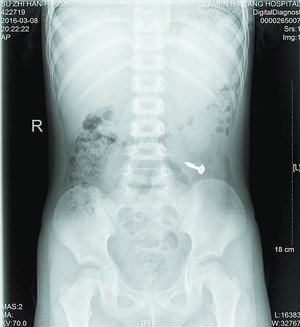

值班的叶医生了解情况后,马上安排女孩做X光片检查,检查影像一出来,大家都吓了一跳,只见女孩左下腹位置清晰地躺着一个金属异物,经再三辨认,确定是一颗螺丝钉。叶医生马上安排女孩转诊小儿外科治疗。儿外科医生接诊后,考虑患者年龄太小,手术损伤大,且目前没有腹痛、腹膜炎等肠穿孔征象,螺丝钉有可能自行排出,便建议随访,叮嘱女孩多吃些富含纤维素的食物,加速螺丝钉的排出。同时告知女孩家长密切观察孩子的身体情况。昨日,女孩再来海沧医院拍片复查,发现螺丝钉已经顺利排出了。